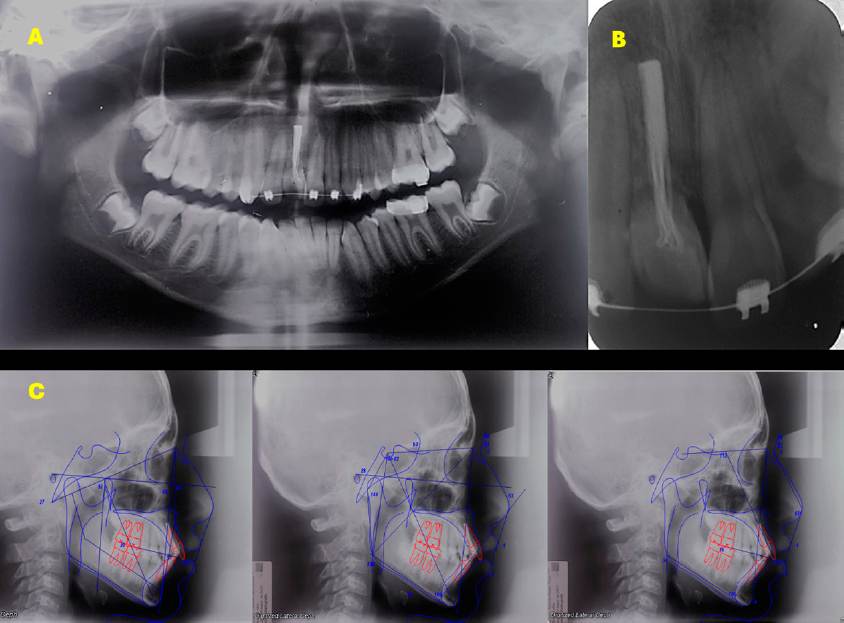

The orthopantomography showed complete dentition, with the presence of the upper central incisor with external root resorption and endodontic seal material. This finding was corroborated with the dentoalveolar radiography. The cephalometric analysis revealed a Class II intermaxillary relationship (ANB 6°), with the mandible in retro position, a slight excess of mandibular body length, maxillary dentoalveolar inclination. In addition, the vertical facial pattern was hyper-divergent (385°) with clockwise growth and brachyfacial pattern. He also had palatalization of the upper right central incisor and proclination of the upper left central incisor (incisor to palatal plane = 112.6°) and the lower central incisor (mandibular plane = 100.1°), increasing the overjet and overbite. Together, these characteristics pointed to a dental malocclusion that needed correction by the values shown in Table 1.

Figure 2 Radiographs. A. Orthopantomography. B. Dentoalveolar of tooth 11, showing external root resorption and root canal treatment. C. Initial cephalometric tracings.